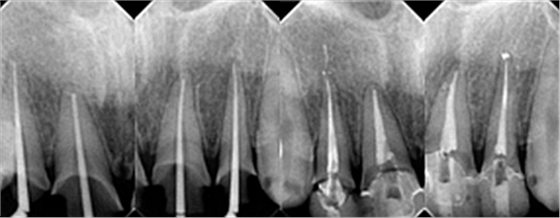

下面是醫(yī)生眼中和ct下的我們

一身病痛啊

牙結石、牙齦炎癥、牙體殘缺、慢性牙髓炎、蛀牙......

治療是從5月份開始的,醫(yī)生給我的主人驗了血,做手術前的準備,還給我們都用超聲波好好的都洗了個澡,把之前依附在我們身上的牙結石都沖了個干凈(齦上潔治術)。治療先從我和其他3個兄弟開始。在麻藥的作用下,我們兄弟4個都被打開了身體,去除了已經(jīng)被蛀牙破壞的牙體,做了根管治療。

根管治療